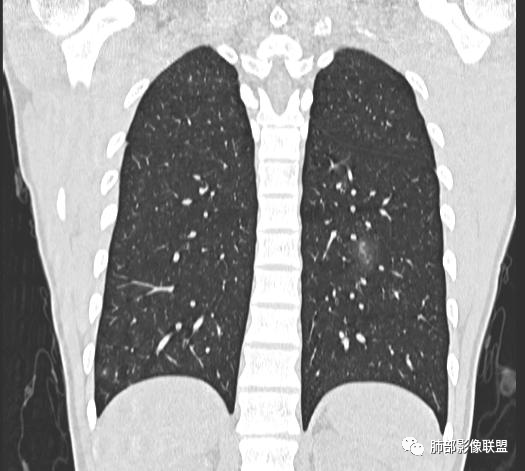

男,19岁

主  诉:发热、全身皮疹2天。

现病史:患者源于2天前受凉后出现发热,最高体温为38.5℃,且颜面部出现少量皮疹,无鼻塞、流涕、咳嗽、咳痰,未在意而未作特殊处理,次日全身皮疹逐渐增多至全身,伴轻度瘙痒,在当地卫生所给予抗病毒、抗感染治疗(具体用药不详)体温有所下降,但皮疹无明显消退,无腹痛、头痛,食欲无明显减退,为进一步诊治,遂于今日急来我院求治,患者目前精神尚可,体力正常,食欲正常,睡眠正常,体重无明显变化,大便正常,排尿正常。

小强:青年,发热,皮疹;双肺散在结节,周围磨玻璃,点晕征,疱疹病毒感染,鉴别荚膜组织胞浆菌,结核。 大雄:青年,急性起病,发热伴全身皮疹2天,抗病毒治疗体温有下降。双肺随机分布大小不等类圆结节,“点晕征”。考虑水痘-疱疹病毒(VZV)血播询问接触史,查体皮疹分布以及形态基本可诊断。 王开金江津中心医院呼吸科:青年男性,起病急,病程短,以发热,皮疹为首发症状,感染指标以单核细胞升高为主,胸部ct双肺多发结界,周围有晕,点晕表现,随机分布,同意於老师意见,水痘疱疹病毒血流感染累及肺。 王秀仙:双肺多发大小不等结节,周围有晕,边缘模糊,呈点晕征表现。青年,急性起病,发热伴全身皮疹2天,抗病毒治疗体温有下降。考虑疱疹病毒。鉴别荚膜组织胞浆菌。 傅昌瑜:19岁男性,发热、全身皮疹2天,单核细胞增高,双肺多发结节,结节边缘见边界不清磨玻璃影。点晕征+发热、全身皮疹+单核细胞增高——考虑水痘-带状疱疹病毒肺炎。 一切∮随缘:年轻男性,发热,皮疹两天,实验室,CRP,PCT增高,影像:双肺多发散在磨玻璃结节,边界欠清,大小不等,呈点晕征改变,以血管束周围分布为主,局部血管束略增粗,其它无明显改变,考虑:1:病毒性肺炎(水痘疱疹病毒?不知道皮肤有无改变)2:真菌(组织胞浆菌,血管侵袭性肺曲霉)3:GPA4:寄生虫(实验室没有看到嗜酸细胞增高) 赵山河:双肺散在结节,周围有晕,边缘模糊,呈点晕征表现。青年,急性起病,发热伴全身皮疹2天,抗病毒治疗体温有下降。考虑水痘—疱疹病毒感染。洪桥爱:青年男性,发热、皮疹2天,伴瘙痒,皮疹于面部首发,之后进展至全身,虽然没有对皮疹进行描述,但是从出疹时间及皮疹进展情况,伴瘙痒,应该就是个水痘患者;CT提示双肺随机分布结节影,部分结节伴有边界不清晕征,考虑水痘血播肺。 刘强:年轻男性,急性起病,皮疹,发热,抗感染治疗体温下降,说明有效。影像表现为散在点晕征,感染类疾病谱(疱疹病毒,真菌,结核),结合年龄,皮肤皮疹,考虑水痘-疱疹病毒性肺炎。 小兜:男性,19岁,发热皮疹两天,颜面部至全身,CRP,降钙素及单核增高。CT示双肺散在小结节,周围伴磨玻璃影,点晕征,考虑为水痘-带状疱疹病毒(varicella-zoster virus,VZV)肺炎 必有路:青年,皮疹+发热+“点晕征”→水痘-疱疹病毒(VZV) 许慧良:青年男性患者,发热、皮疹2天,体温最高38.5℃,第3天皮疹扩展至全身,伴瘙痒,胸部CT:双肺多发随机分布的小结节,结节周边见边界模糊的晕征,考虑水痘病毒感染流心明智:男,19,急性起病,发热伴全身皮疹2天。出疹顺序头→全身,抗病毒有效。胸部CT:两肺多发大小不等类圆形实性小结节影,随机分布,结节周围环绕GGO,边界模糊,呈点晕征。出疹特点是关键,未提示。考虑:血播病毒性肺炎,水痘-疱疹病毒?麻疹?鉴别荚膜组织胞浆菌、TB、血管炎、寄生虫等。 浪迹天涯:病灶多为5-10mm大小结节,结节周围可见磨玻璃样的晕环,常多发,可分布于肺内任何区域,考虑水痘—带状疱疹病肺炎如果短时间内有新的一个区域浸润,更加能说明,